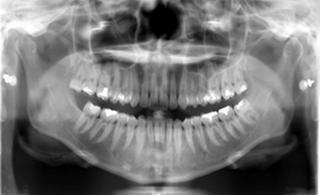

主に、虫歯の治療目的でその広がりの確認のため検査します。

撮影の際は、通常立位の状態で(立位ができない患者様は座位でも可)すべての歯と周りの顎の骨等を1枚の画像として写し出します。(パノラマ撮影)

また、顎関節の描出を目的とした、TMJ(開口位と閉口位で比較)も行っております。